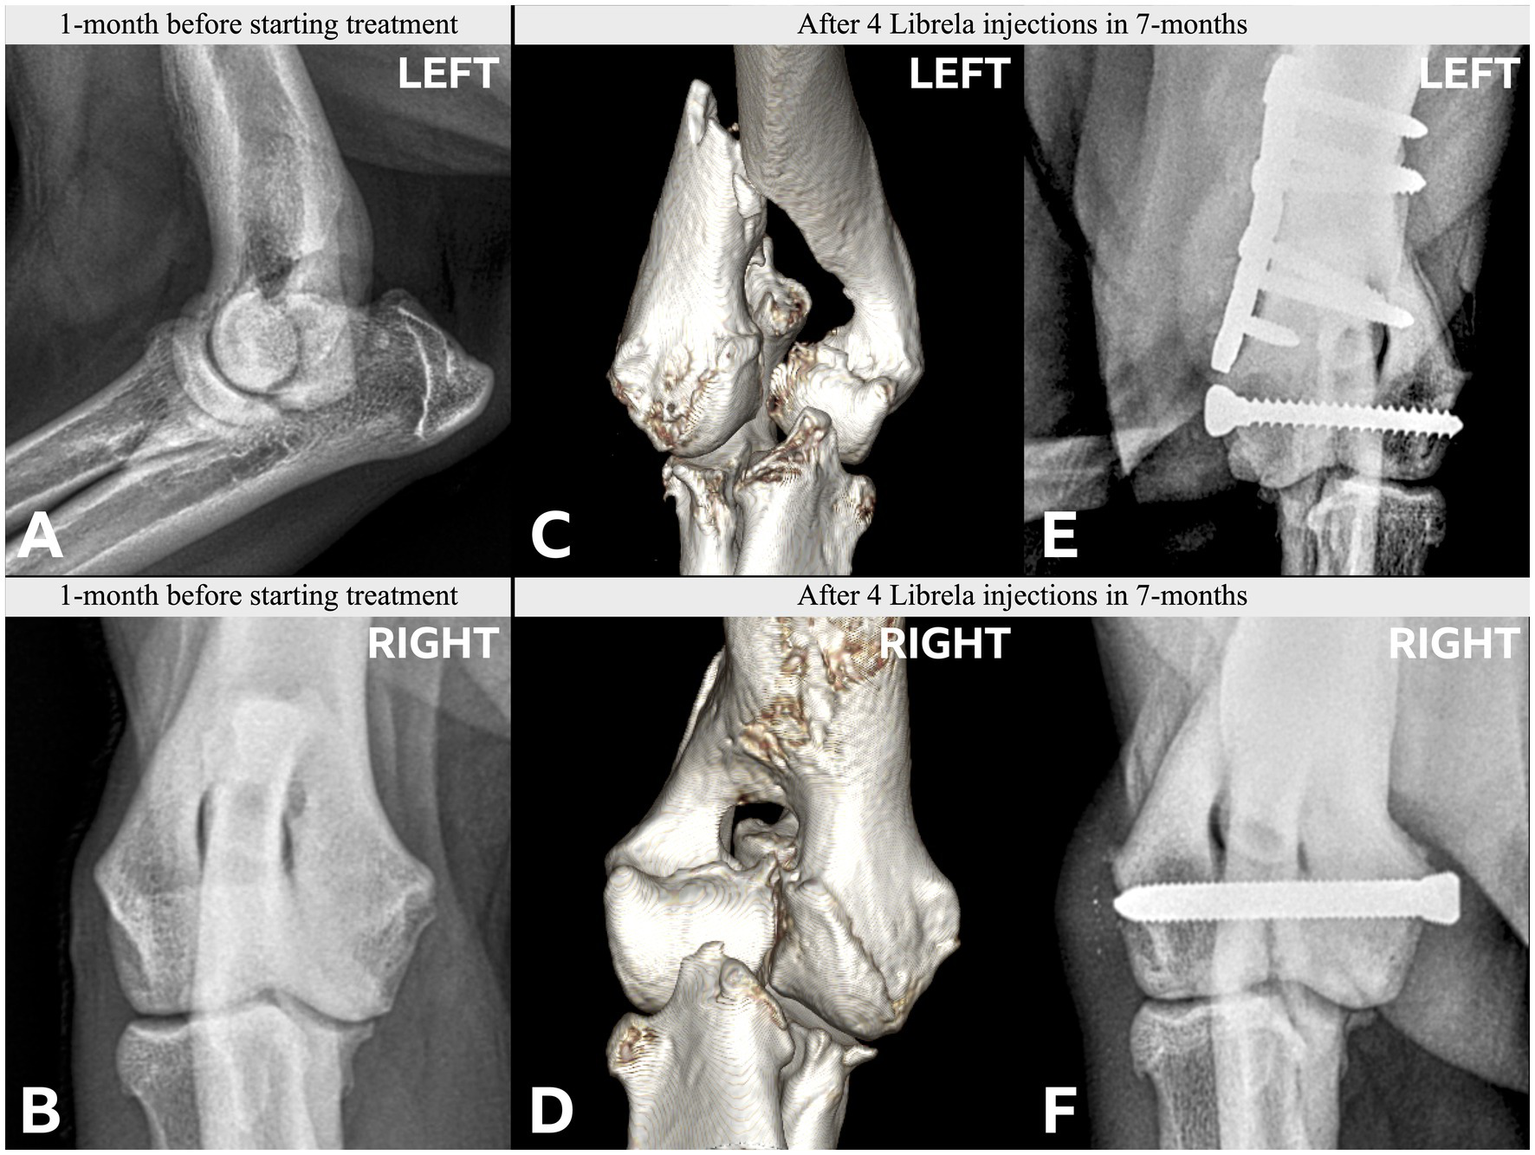

Figure 5

(A) Case 1, a young adult Labrador Retriever. A,B: Orthogonal CT slices demonstrating medial compartment pathology within the right elbow joint. Arrows indicate a medial coronoid process (MCP) fissure and humeral condylar kissing lesion. There is no evidence of a humeral intracondylar fissure (HIF). C,D: Preoperative radiographs obtained after 6 Librela injections reveal a lateral humeral condylar fracture (HCF) with subsequent malunion. A chevron symbol highlights atypical periosteal new bone growth along the medial epicondyle [see Panel 5B(F)]. E,F: Postoperative radiographs acquired 9 months after surgery show successful fracture union, although subchondral bone resorption had progressed. G,H: Severe bilateral seromas that developed after two Librela injections and persisted despite treatment. (B) Case 1—contralateral elbow. A–D: Pre-treatment radiographs and CT scans show MCP remodeling and a humeral condylar lesion consistent with osteochondrosis. E,F: Severe proximal ulnar sclerosis and atypical medial epicondylar periosteal new bone formation were observed after 6 doses of Librela. G,H: Surgical intervention was performed 3 months later. Surgery resulted in successful fracture union, but persistent clinical dysfunction necessitated euthanasia. Histopathological examination: Surgical site infection and septic arthritis were excluded. Findings were consistent with those described in an article on RPOA submitted to the pathologist by the attending specialist (20). AER: The MAH filed a report with an incorrect diagnosis of septic arthritis (Supplementary Figure S1).

Figure 6

Case 4 is a Labrador Retriever with no history of trauma. (A,B) Pre-treatment radiographs taken aged 8.5-years. A pre-treatment left craniocaudal radiograph was not acquired. (C,D) Post-Librela radiographs demonstrate a left lateral HCF with an atypical medial epicondylar periosteal reaction (C) and a right HIF (D). (E,F) Immediate post-operative radiographs. AER: After considering the lack of trauma and atypical signalment for HIF, the attending specialist filed an AER to the Veterinary Medicines Directorate (VMD) for suspected RPOA. This report was shared with the MAH, who filed a report for non-serious “arthritis”, with an outcome of recovered/resolving (Supplementary Figure S3).